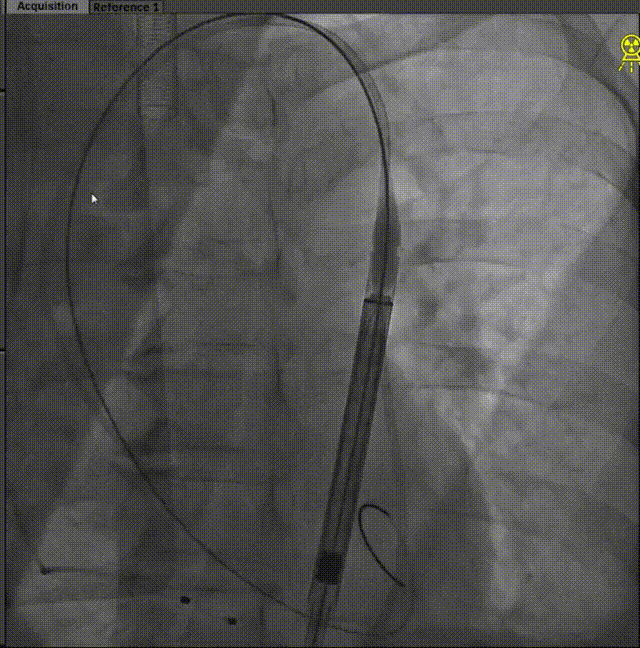

中段释放

快速 control pacing

LAO角度下评估

瓣膜低端打平

再次评估后 最终释放

关闭递送系统及最终造影